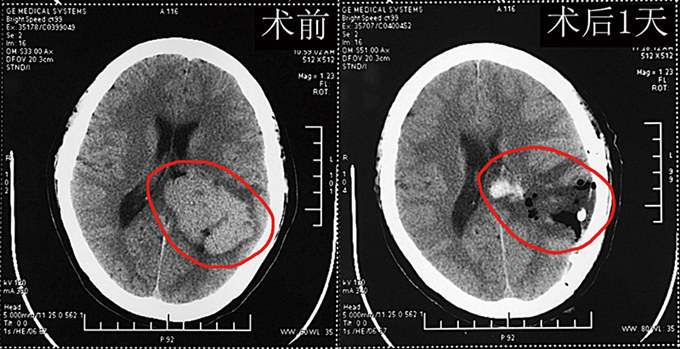

术后复查,郭阿姨的头颅CT及MRI显示肿瘤全切除,无残留。邹仰光 摄

在完善相关检查及做好术前准备后,在蔡少明主任带领下的显微外科手术团队成功为郭阿姨实施巨大左侧脑室三角区脑膜瘤切除术。手术取靠近肿瘤主体的颞顶枕马蹄形切口开颅,采用经脑沟入路,绕开功能区,保护脑室内侧壁上的丘纹静脉,避免脑室内脉络丛损伤出血,仔细分离肿瘤包膜和供瘤血管,先经瘤内减压,再分块切除肿瘤,完成显微镜下肿瘤全切除。历时7小时,手术在对脑组织做到最大程度保护的基础上顺利完成,术中出血少,术后患者神志转清,言语清晰,四肢肌力、肌张力正常,记忆力正常,无神经系统功能缺失。